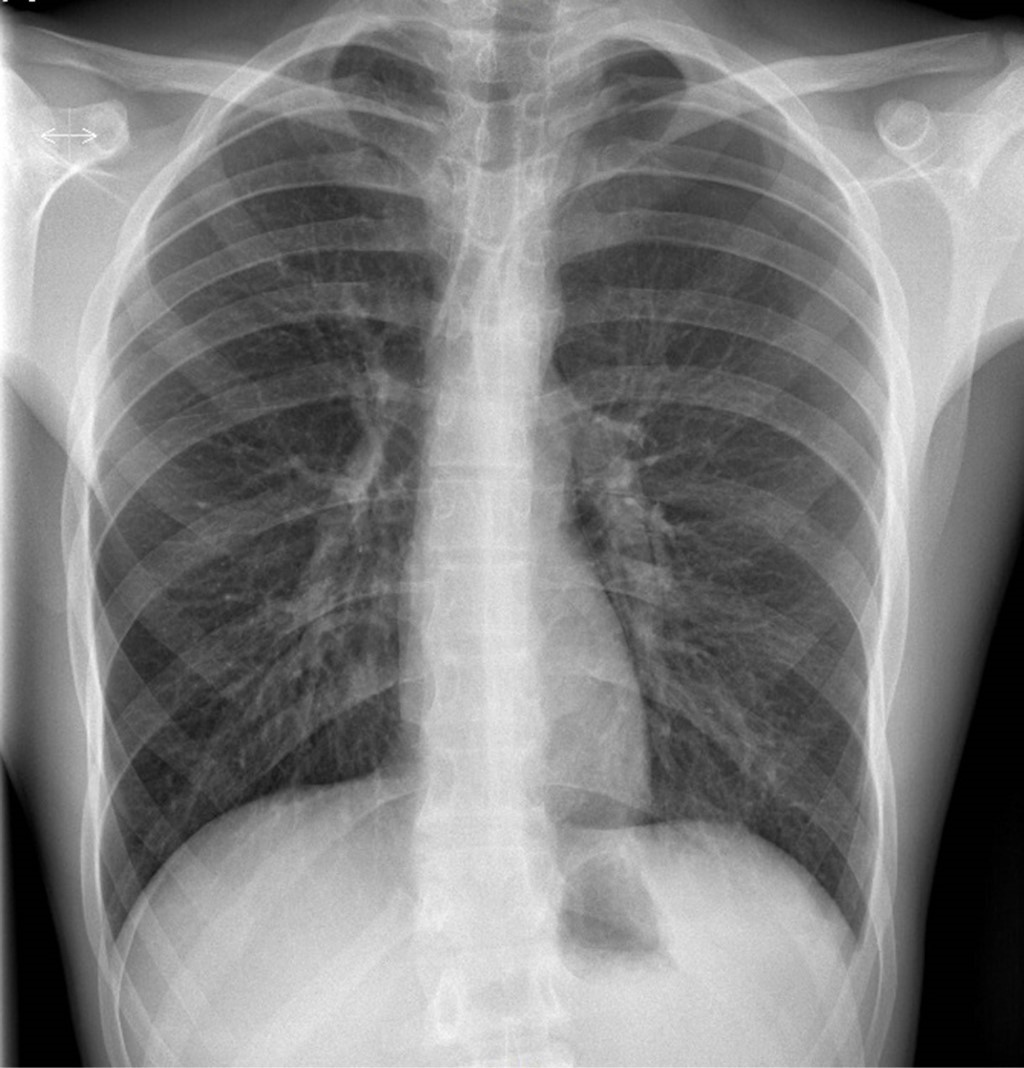

Seis horas después, refiere dolor intenso a pesar de analgesia, por lo que se toma nueva radiografía, observando aumento del neumotórax al 20% (Figura 2). Se decide colocación de drenaje torácico en segundo espacio intercostal izquierdo con posterior aspiración con Pleur-evac®. El control radiológico a las 12 horas se observa con mejoría, por lo que se cierra aspiración. Sin embargo, a las 18 horas el paciente presenta empeoramiento del dolor torácico de características pleuríticas, a lo que se agregó drenaje de líquido hemático de aproximadamente 300 mL, sospechando de hemotórax. El hematocrito fue de 48%.

Figura 2